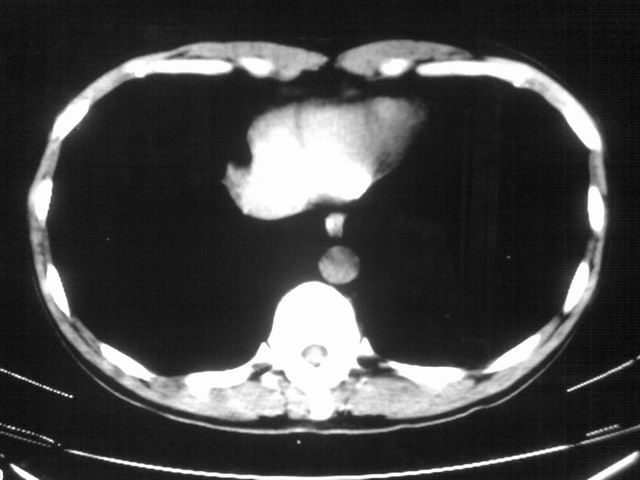

以下是引用苯小孩在2007-4-24 19:46:00的发言:[br]左下肺内侧基底段,见类圆形病灶,边缘清晰光滑.强化后轻中度强化.<平扫第4层面似有从腹主动脉相连血管影,可惜强化扫描这层没有抓住>考虑:左下肺隔离症.建议dsa或薄层强化重建观察.

以下是引用同在2007-4-24 20:11:00的发言:[br]考虑肺隔离症